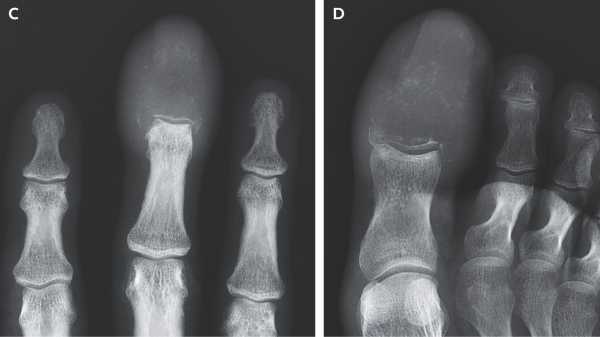

Дивний набряк пальців рук і ніг чоловіка показав, що рак «повністю замінив» кістки ураженнями.